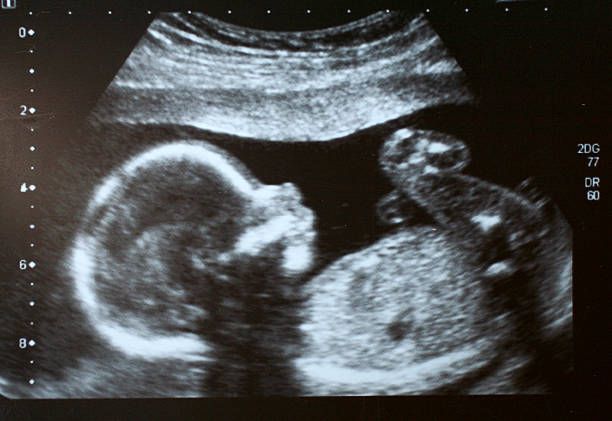

Στο όχι πολύ μακρινό παρελθόν, έως 50 χρόνια πριν, η άμβλωση (εκ του ρήματος αμβλίσκω = αποβάλλω διά βίαιων μέσων) θεωρείτο «προοδευτισμός» και «δικαίωμα» για κάθε γυναίκα. Με την εξέλιξη, όμως, της τεχνολογίας ανακαλύψαμε και μαθαίνουμε ακόμη όλα τα θαυμαστά στάδια της γέννησης και της εξέλιξης μιας ζωής μέσα στο σώμα μιας κυοφορούσας γυναίκας. Οι αποκαλύψεις αυτές έκαναν σαφές ότι το έμβρυο δεν ανήκει στο σώμα της γυναίκας, αλλά είναι άλλο σώμα. Ένας άλλος άνθρωπος! Σώμα της γυναίκας είναι λ.χ. τα μάτια της, τα οποία φυσικά έχει το δικαίωμα να τα βγάλει όποτε και με όποιον τρόπο θέλει. Τη ζωή, όμως, που φέρει μέσα της έχει ιερή υποχρέωση να την προστατεύει.